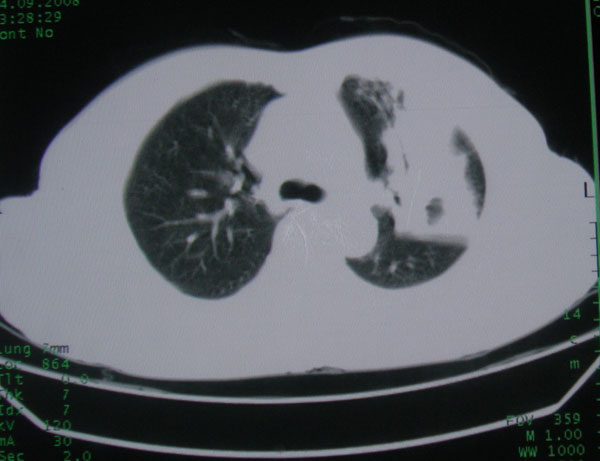

患者男性58岁因二周前起咳嗽,今天胸片示左上肺占位性病变行ct检查,无发热,无咯血痰.

左肺上叶病灶,实变但见含气支气管、空洞但未见壁内结节及积液;

初学者。。。左肺空洞性病变,并可见阻塞性肺不张改变,鉴于患者为老年男性,且临床症状仅有咳嗽,全身中毒症状不明显,所以我首先考虑为左肺癌性空洞并左侧肺门淋巴结转移伴左肺阻塞性肺不张。结核性空洞放于第二位考虑,可以进行相关实验室检查。希望能有病理结果,谢谢!!!!!

左肺上叶实变影,内见支气管充气征及空洞影,病人年龄较大,无发热及结核中毒症状,心影左移,未见纵隔淋巴结肿大;不知实验室检查结果如何?有否嗜酸细胞增多,有没有进行治疗?就目前资料首先考虑1.感染性病变,2.慢性嗜酸性肺炎?可结合实验室检查并短期治疗复查,肺癌不能排除。